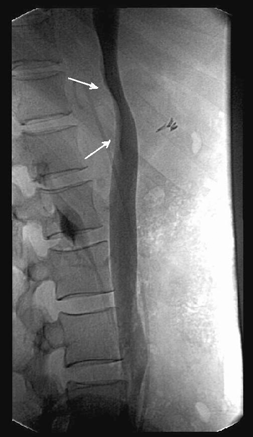

Важное место среди инструментальных методов исследования опухолей надпочечников в настоящее время занимает УЗИ (рис. 1). Это, в первую очередь, обусловлено простотой его выполнения, высокой достоверностью полученных результатов, а также быстротой и доступностью его выполнения (Демидов В.Н. и др., 1991). По мнению большинства авторов, УЗИ позволяет выявить опухоли надпочечников при минимальном диаметре от 1 до 2 см (Gunhter R.W., 1984; Zografos G.C. et al., 1994).

Рисунок 1. УЗИ — опухоль правого надпочечника

Значительно улучшает качество диагностики опухолей надпочечников использование КТ. Минимальная величина опухоли, определяемая этим методом, составляет от 0,5 до 1 см (Бондаренко В.О., 1986). КТ позволяет определить топографию надпочечников, форму, величину, структуру. Точность КТ в диагностике опухолей надпочечников в настоящее время составляет 80–95,7% (Авдеева Т.Ф. и др., 1992) (рис. 2).

Рисунок 2. КТ — опухоль (аденома) левого надпочечника

Наряду с преимуществами КТ имеет и ряд недостатков. При больших размерах опухоли трудно определить ее исходную локализацию, распространенность на другие органы и магистральные сосуды (Григорян С.В. и др., 1986). Основным методом, позволяющим ответить на данные вопросы, является АГ. Но, несмотря на тридцатилетний опыт применения АГ при опухолях надпочечников, до настоящего времени не установлено специфических ангиографических признаков, присущих какой-либо определенной гистологической форме опухоли. Тем не менее ангиографическая картина в большинстве случаев достаточно характерна, чтобы установить исходную локализацию опухоли, степень ее васкуляризации, источники кровоснабжения и распространение на окружающие органы и ткани (рис. 3, 4).

Рисунок 3. Селективная артериография (артериальная фаза) — умеренно васкуляризированная опухоль (феохромоцитома) правого надпочечника

Рисунок 4. Ангиография (паренхиматозная фаза) — умеренно васкуляризированная опухоль (феохромоцитома) правого надпочечника

По данным различных авторов, точность ангиографической диагностики опухолей надпочечников составляет 78–95% (Kohler R. et al., 1976; Zografos G.C. et al., 1994). При правосторонней локализации опухоли, особенно больших размеров, для выявления взаимосвязи с нижней полой веной необходимо выполнение нижней каваграфии, желательно в двух проекциях (рис. 5, 6).